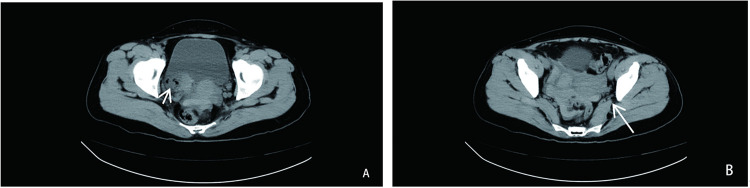

Female external genital injuries mainly include sexual-related injuries and accidental injuries. Severe cases may experience rapid and massive bleeding, with possible foreign body retention in the body or concurrent injuries to adjacent organs such as the rectum and bladder. Most of these cases require surgical treatment, and the intraoperative situation is complex and changeable. We report a patient with a penetrating injury of the genital tract and foreign body retention in the body, who was successfully treated using the laparoscopic combined with transvaginal full-layer suture technique. Compared with the traditional transvaginal approach, this method can comprehensively explore the lacerations and surrounding organs of the cavity, and thoroughly clean up residual foreign bodies in the body. This paper explores the safety, feasibility, related surgical techniques, and perioperative precautions of this technique in the treatment of genital tract penetrating injuries.